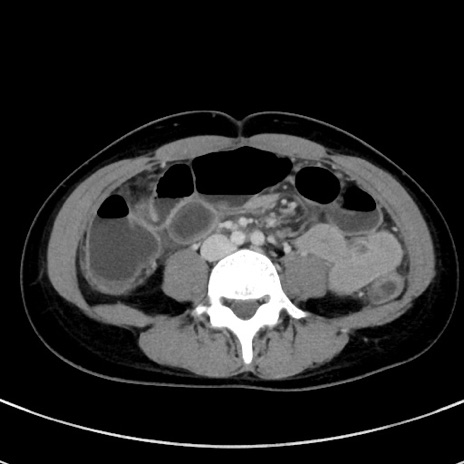

症例17(横断像)

【症例】20歳代女性

【主訴】嘔吐、下腹部痛

【現病歴】昨日夕食後に嘔吐し下腹部痛が出現。本日になっても嘔吐持続し改善しないため来院。

【身体所見】意識清明、BT 37.2℃、BP 108/67mmHg、腹部:平坦、やや硬、下腹部正中から右にかけて圧痛あり、反跳痛軽度あり、tapping pain(+)。

【データ】WBC 13600、CRP 14.94